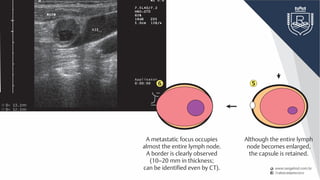

Although the entire lymph

node becomes enlarged,

the capsule is retained.

A metastatic focus occupies

almost the entire lymph node.

A border is clearly observed

(10–20 mm in thickness;

can be identified even by CT).